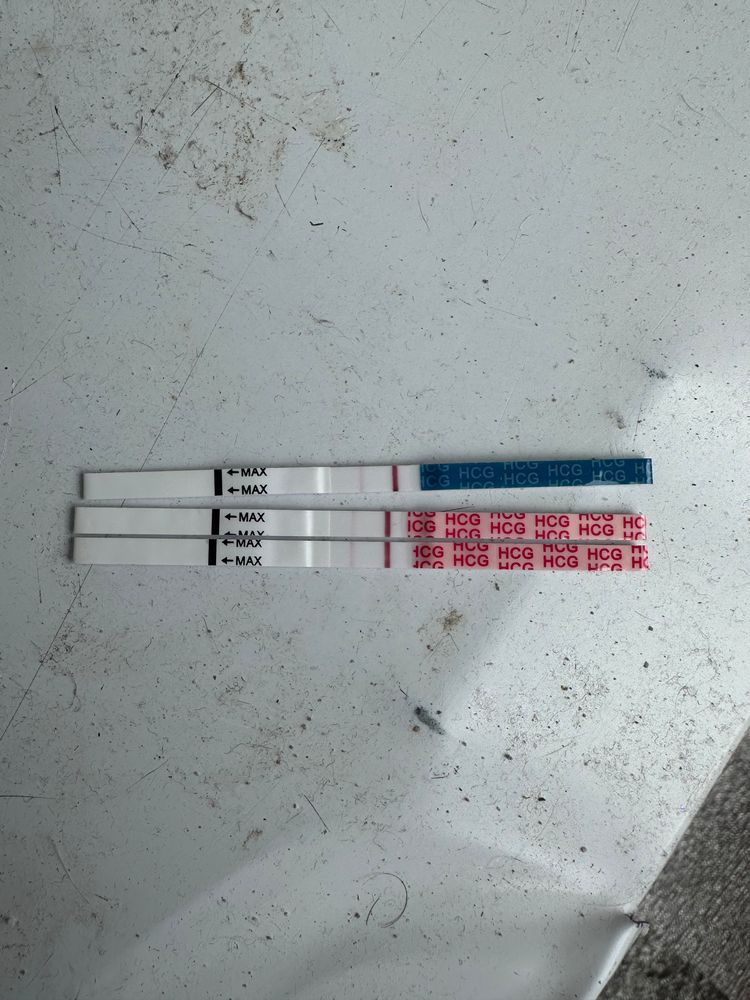

Девачки, почитала всех и короче пошла тесто манить , не могу уснуть теперь 😂😂😂😂 во что получилось напоминаю на 6 дпо

тест на о сегодняшний

Тест с верху старый 2 цикла назад

Тест с верху старый 2 цикла назад

Тест с верху старый 2 цикла назад

Тест с верху старый 2 цикла назад

Алина Горева, что-то есть, но мне кажется тест потек(

лучше переделать